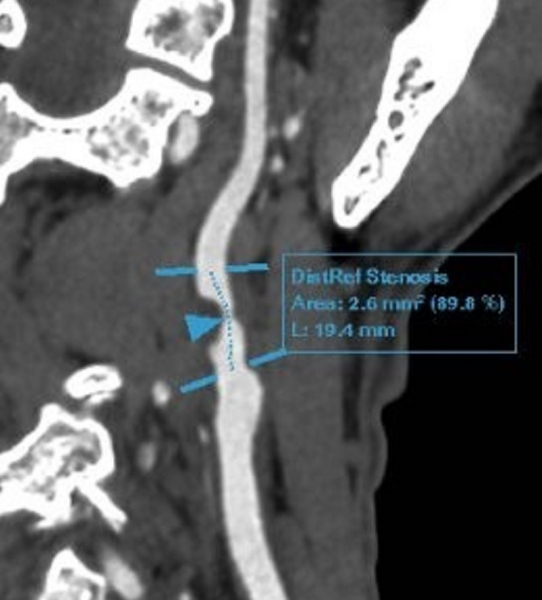

Ông Đ được bác sĩ chỉ định thực hiện xét nghiệm và các kỹ thuật chẩn đoán hình ảnh chuyên sâu tìm nguyên nhân gây đau đầu. Sau đó, ông được chẩn đoán mắc bệnh động mạch cảnh do xơ vữa, hẹp nặng 90% động mạch cảnh trong bên phải, lóc tách nhỏ gốc động mạch cảnh trong bên trái. Bệnh động mạch vành mạn tính. Rối loạn lipid máu.

“Trường hợp của ông Đ đã hút thuốc lá gần 30 năm (tương đương hơn 6.000 bao), đi khám vì các cơn đau đầu nhẹ thoáng qua nhưng đã phát hiện mảng xơ vữa gây hẹp 90% gốc động mạch trong phải, lóc tách nhỏ gốc động mạch cảnh trong. Đây là minh chứng rõ ràng cho tác động nghiêm trọng và âm thầm của thuốc lá lên hệ mạch máu não và tim mạch. Bên cạnh đó, khi thấy các dấu hiệu không rõ ràng như: Chóng mặt, buồn nôn, yếu liệt tay chân hay rối loạn ý thức, người bệnh vẫn tiềm ẩn nguy cơ cao bị đột quỵ nếu không được phát hiện và can thiệp kịp thời”, BS Nam nhấn mạnh.

Phim chụp tổn thương của bệnh nhân.